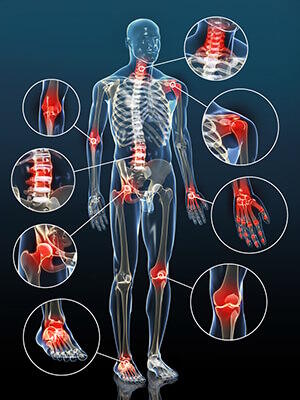

Etant donné sa puissante activité analgésique, le PEA est souvent présenté comme un antidouleur naturel universel. Il permet en effet de lutter contre de nombreuses douleurs, qu’elles soient aiguës ou chroniques. Le PEA permet de soulager des douleurs d’origine différente : les douleurs inflammatoires, les douleurs neuropathiques et les douleurs mixtes, qui peuvent être à la fois inflammatoires et neuropathiques1,2,3..